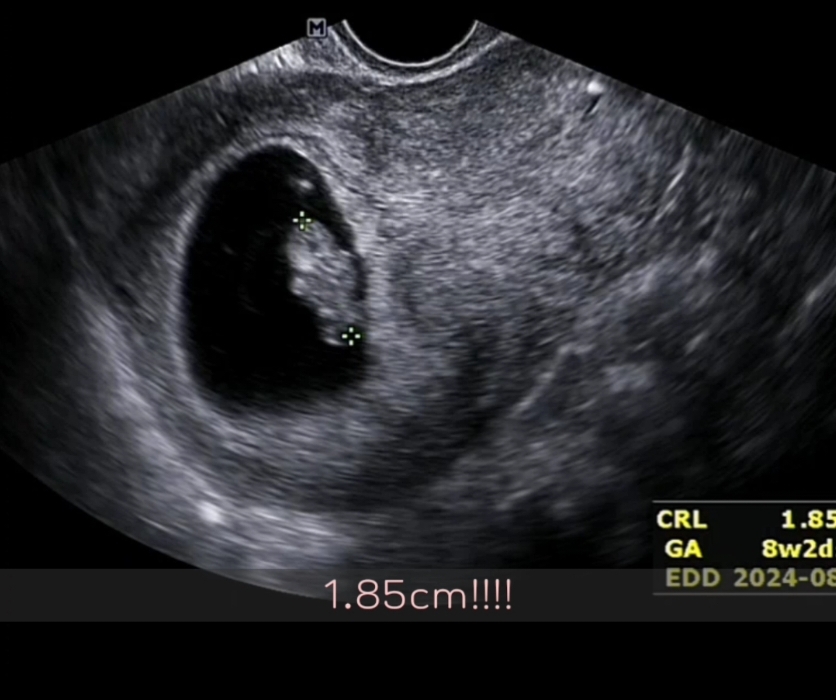

8주4일 젤리곰으로 가는 길

오늘이 8주4일차. 병원가서 조그만 팔과 다리가 나오기 시작한 미니 젤리곰을 만나고 왔어요! 1.85센티 작고 소중한 아가. 41세 노산이라 매일매일이 조심스럽고 지난 2주동안 뱃속에 아기가 잘 있는지 불안하고 설레여하며 보냈는데 너무나 건강하게 주수에 맞게 잘 크고 있다고 하셔서 한시름 놓았어요ㅜㅜ 산전검사 결과도 모두 정상이라 기쁜 하루네요~